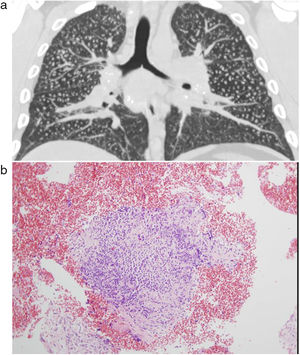

Tables 3 and 4 show the radiological readings of the chest X-ray and chest HRCT. In 21 cases, we had to resort to a histological study to achieve greater diagnostic certainty. The presence of nodules characteristic of silicosis was observed in 17 (81%), granulomas coexisted in the parenchyma and lymph nodes in 3 patients, and 3 cases showed an interstitial pattern with characteristics highly suggestive of usual interstitial pneumonia.

Chest HRCT is well known to increase sensitivity in the detection of progressive massive fibrosis (PMF).32 Nodular pattern findings, subpleural involvement and lymphadenopathies are similar to those of classic silicosis,33 although the presence of ground glass patterns of moderate extension in 30% of patients in our series should be noted, in addition to the existence of the usual nodules (Fig. 1). Several of the cases described by the Australian and Italian authors10,23 were significant for the presence of lymphocytosis in bronchoalveolar lavage, findings not described in classic silicosis. All this suggests a different form of the disease, probably more disseminated and aggressive than usual, which can develop more rapidly to an irreversible, fibrosing process. In our series, 10 patients met the criteria for accelerated silicosis.34 This group is too small to draw meaningful conclusions, but a profile is emerging of young people employed in cutting and polishing stone with increased use of conglomerates, who develop PMF (Fig. 2) and a tendency to lower lung function values. The histological and mineralogical study of samples obtained by transbronchial cryobiopsy35 helped exclude sarcoidosis in young people who showed a short latency period from the start of exposure (Fig. 3), and in other cases it revealed patterns of usual interstitial pneumonia associated with the deposit of silica particles (Fig. 4),36,37 which introduces therapeutic prospects not yet addressed in this disease.38